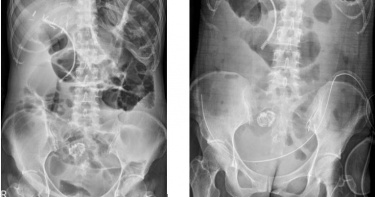

50歲的王先生是一位上班族,於一年半前因大便習慣改變,總感覺解便不乾淨有異物感,直到出現血便,王先生健檢時被診斷為超低位直腸癌第三期,腫瘤有7公分大,經放射線治療縮小至4公分,醫師仍建議需開刀切除腫瘤但無法保留肛門。由於術後需使用人工肛門,王先生驚愕之餘對手術相當擔憂,轉介至中國醫藥大學附設醫院大腸直腸肛門外科尋求陳奕彰醫師門診,陳醫師建議進行化學治療6次,再決定後續治療方針。由於化療後腫瘤縮小有限,陳奕彰醫師亦建議手術摘除腫瘤,核磁共振顯示,王先生的直腸腫瘤非常接近肛門但並無侵犯括約肌,經陳奕彰醫師評估建議達文西機械手臂手術切除腫瘤,能保留完整肛門。王先生於去(112)年10月接受達文西手術開刀,手術傷口五處,每處僅1公分,術後完整保留肛門,術後第8天出院,追蹤半年恢復情況良好,目前並無復發跡象。根據國民健康署110年最新癌症登記資料顯示,大腸直腸癌高居10大癌症發生人數第二名,平均每年新增約1萬6千多人。陳奕彰醫師說明,超低位直腸癌是腫瘤距離肛門口六公分以內,貼近直腸肛門吻合線,一般手術可能會直接進行直腸肛門切除以及永久性人工肛門。對於超低位直腸癌病人如王先生,其核磁共振影像顯示腫瘤已侵犯腸壁漿膜層以上或局部淋巴結有轉移情況,因此建議先安排術前放射治療並配合化學治療,以降低術後腫瘤局部復發機會,也可以縮小腫瘤體積而進一步達到肛門保留手術。大腸直腸肛門外科代主任張伸吉醫師指出,相比一般微創手術,達文西機械手臂可提供高解析3D立體視野可放大至10倍,可填補因平面2D而無法區分手術位置深淺的缺點;機械手臂可達到真人手腕靈活和準確且可模仿雙手做旋轉、抓取、捏夾動作,消除不必要的顫抖,更重要的,相較於一般微創手術,達文西機器手臂可以在狹小骨盆腔進行複雜手術,例如低位直腸癌和攝護腺手術等,避免傷害到排便、排尿和性功能神經。陳奕彰醫師的論文研究也發現達文西機械手臂和一般微創手術相比能清除更多轉移淋巴結和較少的手術併發症,此論文也於今年美國內視鏡醫學會雜誌接受刊登,陳醫師並將於6月獲邀至美國醫學年會演講。健保署已於去年3月將達文西手術納入直腸癌部分健保給付後,成功案例約70台,陳奕彰醫師也呼籲,定期接受篩檢可減少晚期大腸癌發生率,早期發現、早期治療。九成大腸直腸癌好發於50歲以上之病人,隨年齡增加而升高,男性發生率為女性的1.5倍。許多病人在疾病早期幾乎沒有明顯症狀,等到出現便血、排便習慣改變、貧血、腹痛、體重減輕時,已經是第3、4期。許多病人因懼怕人工肛門而拒絕手術、延遲病情,達文西機械手臂可達到精準切割,保留完整肛門和排尿、排便和性功能這些微小神經,加速術後恢復。